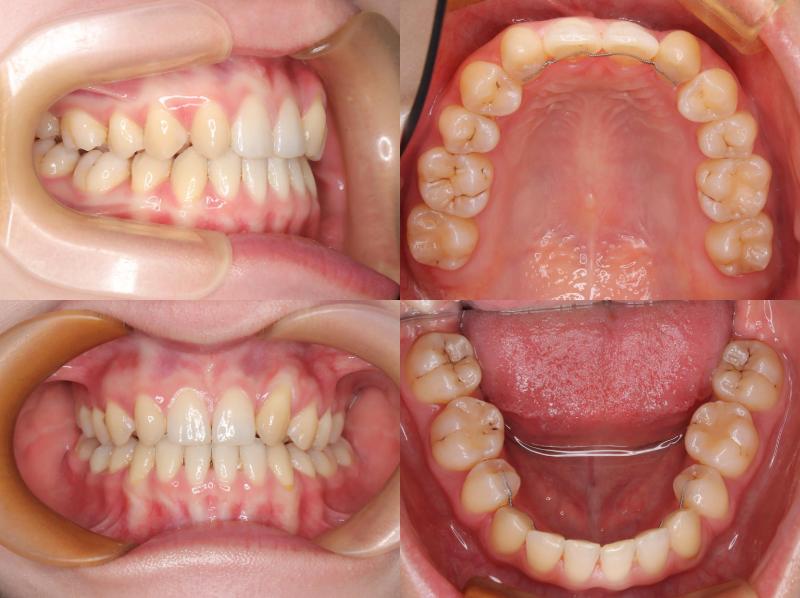

治療の結果、口元の突出感とディープバイトの改善が認められ、より自然で調和のとれた横顔を得ることができました。

この症例では、上顎前歯唇側にアンカースクリューを2本埋入し、上顎前歯の圧下を行うことでリスクをコントロールしました。